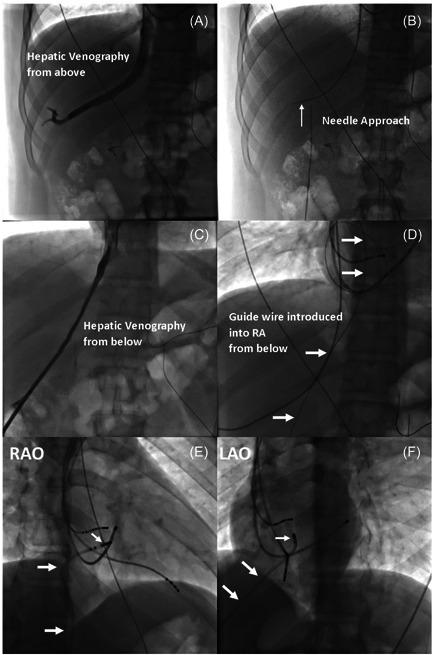

The objective of the study was to conduct a systematic review to describe and compare the different approaches for performing cardiac electrophysiology (EP) procedures in patients with interrupted inferior vena cava (IVC) or equivalent entities causing IVC obstruction.

The analysis included 142 patients (mean age 48.9 years; 48% female) undergoing 143 procedures. Obstruction of the IVC was not known before the index procedure in 54% of patients. Congenital interruption of IVC was the most frequent cause (80%); and, associated congenital heart disease (CHD) was observed in 43% of patients in this setting. The superior approach for ablation was the most frequently used strategy (52%), followed by inferior approach via the azygos or hemiazygos vein (24%), transhepatic approach (14%), and retroaortic approach (10%). Electroanatomical mapping (58%), use of long sheaths (41%), intracardiac echocardiography (19%), transesophageal echocardiography (15%) and remote controlled magnetic navigation (13%) were used as adjuncts to aid performance. Ablation was successful in 135 of 140 procedures in which outcomes were reported. Major complications were only reported in patients undergoing AF ablation, including two patients with pericardial effusion, one of whom required surgical repair, and another patient who died after inadvertent entry into an undiagnosed atrioesophageal fistula from a previous procedure.

The superior approach is most frequent approach for performing EP procedures in the setting of obstructed IVC. Transhepatic approach is a feasible alternative, and may provide a "familiar approach" for transseptal access when it is required. Adjunctive use of long sheaths, intravascular echocardiography, electro-anatomical mapping and remote magnetic navigation may be helpful, especially if there is associated complex CHD. With careful planning, EP procedures can usually be successfully performed with a low risk of complications.